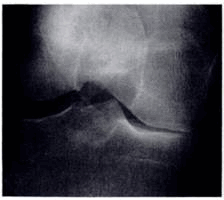

(Слева) Рентгенография в ПЗ проекции: ОА латерального отдела коленною сустава ва. На фоне вальгусной деформации визуализируются остеофиты и определяется полная утрата хряща. Несмотря на то, что поражение медиального отдела считается типичным при ОА, поражение латеральною отдела может доминировать.

(Справа) Рентгенография в ПЗ проекции: пример раннею ОА, характеризующегося исключительно формированием остеофитов. При рентгенографии, выполненной с осевой нагрузкой, признаки нарушения соосности и утраты хряща не определяются. Остеофиты визуализируются только в области межмыщелковго возвышения большеберцовой кости. (Слева) Рентгенография в боковой проекции, этот же пациент: определяются остеофиты надколенника. Также визуализируется субхондральный остеофит поверхности мыщелка бедренной кости. Субхондральные остеофиты часто сопровождаются фокальным дефектом хряща, что в этом случае подтвердилось при МРТ. Обратите внимание на отсутствие свободных тел.

(Справа) МРТ, сагиттальная проекция, режим протонной плотности с подавлением сигнала от жира: еще одно свободное тело у этого же пациента. Визуализируется субхондральный остеофит с дефектом хряща. Стабилизирующие структуры не изменены. Ранний ОА характеризуется наличием свободных тел, а также субхондральных остеофитов с ассоциированными дефектами хряща. При рентгенографии эти признаки не определяются, поэтому МРТ, в данном случае, более информативна.

(Слева) Рентгенография в ПЗ проекции: истончение хряща в медиальном отделе коленного сустава и крупный субхондральный остеофит с минимальными краевыми остеофитами.

(Справа) МРТ, сагиттальная проекция, режим Т2 с подавлением сигнала от жира: срез выполнен несколько медиальнее субхондрального остеофита, однако здесь определяется обширный дефект хряща нагружаемой зоны медиального мыщелка бедренной кости, наряду с признаками расслоения. Сигнал от субхондральных остеофитов достоверно ассоциируется с повреждением хряща. (Слева) МР-артрография, сагиттальная проекция, режим Т2 с подавлением сигнала от жира: определяется обширный дефект хряща в области блока, а также признаки отека костного мозга. Необходимо скрупулезно исследовать область блока, оценка протяженности повреждения которого может быть затруднена, поскольку его поверхность обычно не ортогональна плоскости исследования.

(Справа) Артроскопическая фотография, этот же пациент: определяется обширный полнослойный дефект в области блока. (Слева) МРТ, аксиальная проекция, режим Т2 с подавлением сигнала от жира: фокальные фиссуры хряща надколенника у его вершины, достигающие уровня субхондральной кости. Обратите внимание на то, что дефект распространяется латерально в костной пластинке; здесь следует предполагать расслоение.

(Справа) МРТ, аксиальная проекция, режим Т2 с подавлением сигнала от жира: сигнал повышенной интенсивности и неполный дефект хряща преимущественно латеральной фасетки надколенника, который особенно хорошо визуализируется на фоне выпота. Также определяется отек подлежащего костного мозга. Повреждение хряща соответствует 2-3 степени.